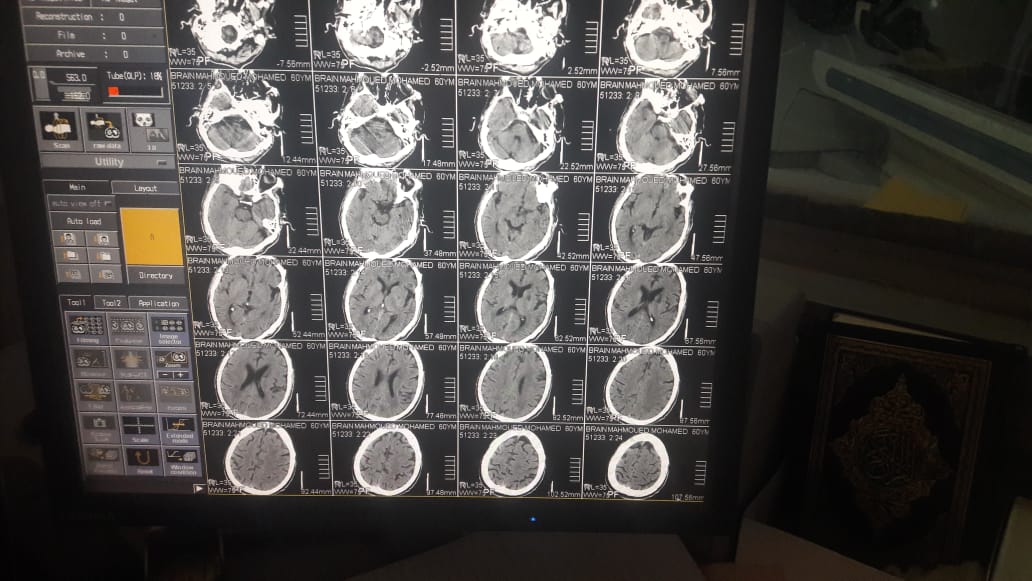

Discuss causes and management of stroke in children